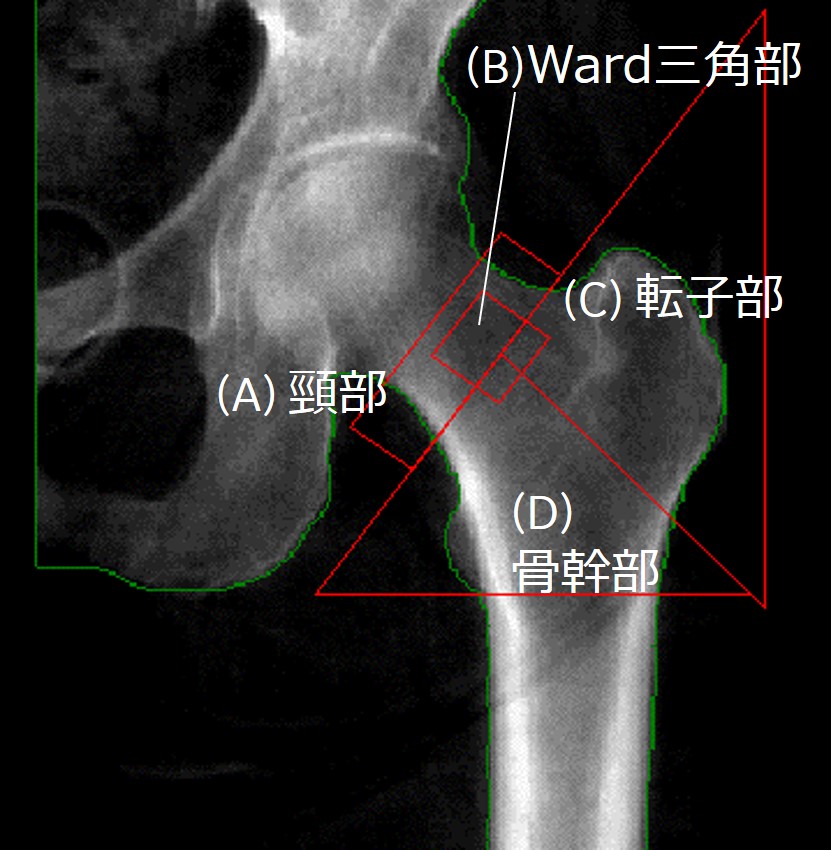

【大腿骨近位部骨密度測定】

・大腿骨骨幹部軸と体軸が平行になるように測定する。

・股関節内旋・外旋は、骨密度に大きな影響を与える。小転子が小さく見えるのが適切な回旋である(図5)。小転子が大きく見えるのは外旋が強く、全く見えないのは内旋が強い。

・頚部、近位全体を計測値として用いる。

・近位全体とは、頸部・転子部・骨幹部を合わせた領域を示す(図6)。

・頚部が診断に適切な部位であるが、近位全体のYAM%もしくはTスコアが低い場合には、近位全体の結果を用いる。

・経過観察には近位全体が適する。

・ワード三角部は診断・経過観察いずれにも用いない。 その理由は、領域が小さく再現性が不良。また、もともと骨密度の低い部分で過剰診断となりうる。

・左右いずれの測定でも問題はない。ただし、経過観察においては同側を測定する。

ClinicalTips03_06.jpg

図5. 大腿骨近位部

(A) 背側から見た大腿骨近位部

(B) 腹側から見た大腿骨近位部

頸部が最も正面にあり、広く見えるとき、小転子は小さく見える

(出典:McMinn RMH, Hutchings RT, Pegington J, and Abrahams PH. 1993 Color atlas of human anatomy, 3rd ed by permission of Mosby International.)

ClinicalTips03_07.jpg

図6.大腿骨近位部の領域

(A)大腿骨頸部 (B)Ward三角部 (C)転子部 (D)骨幹部

大腿骨近位部は(A)(C)(D)をあわせた領域。

小転子が小さく見え、骨幹部がスキャン方向と平行になっている。